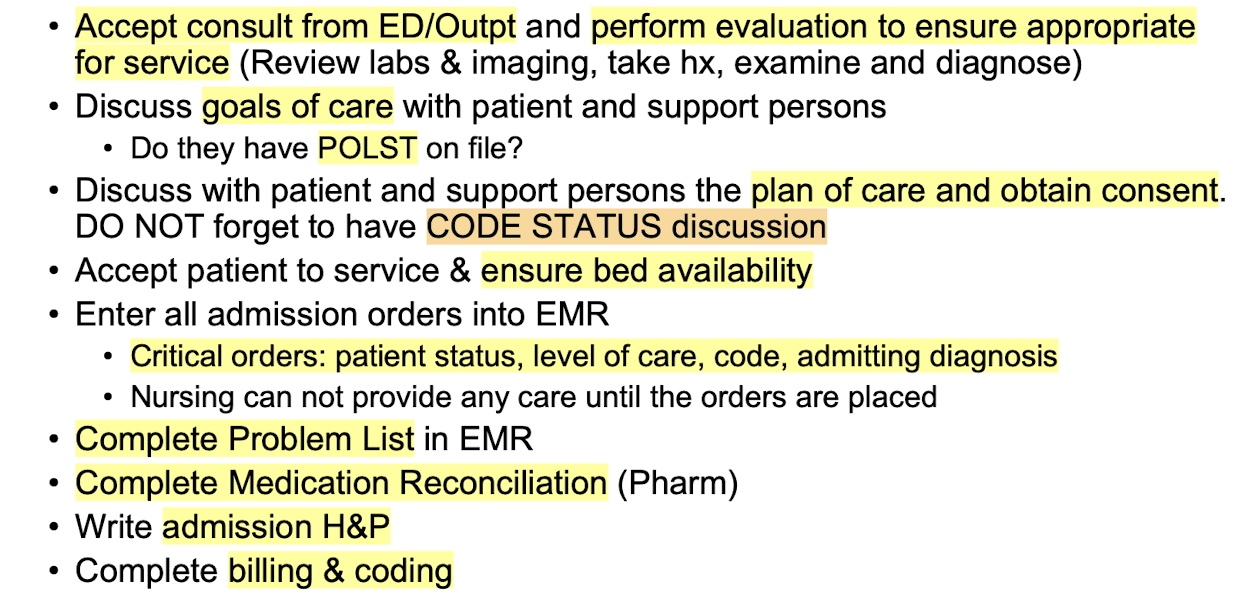

Admission

-Care plan created

-Orders are placed, plan is set in motion

-Notify consult services need to evaluate and treat based on orders

-Admission documents are completed

Steps:

Critical orders: patient status, level of care, code status, admitting diagnosis